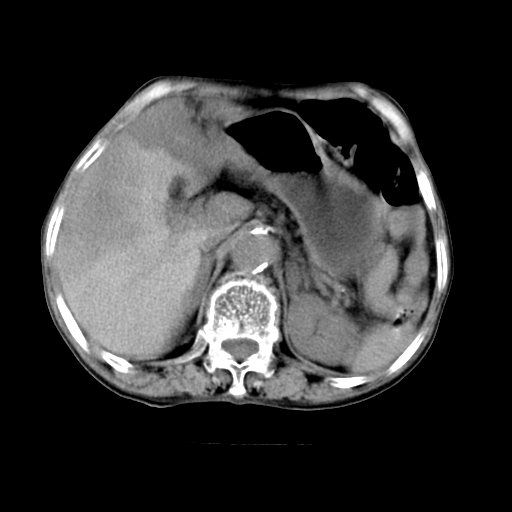

标题: CT19149:女,68岁,腹胀、恶心两周。 [打印本页]

女,68岁,腹胀、恶心两周,先做ct平扫,当时家属不同意强化,6天后家属要求增强扫描。

1、胃窦癌; 2、局灶性脂肪肝。

1、胃窦癌?建议行胃镜!; 2、局灶性脂肪肝。

1.局灶性脂肪肝;2.胃窦癌可能,建议行进一步检查。